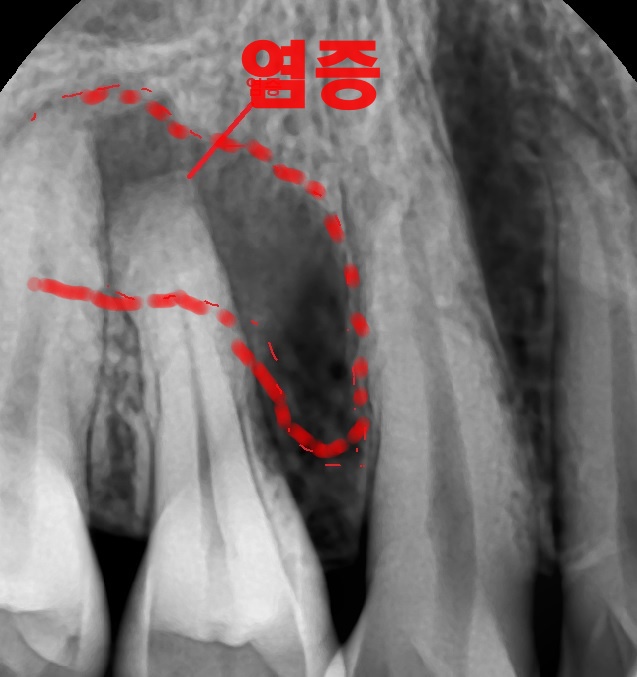

​염증 소견이 두 개 치아에 걸쳐서 보였던 환자 사례입니다. 표면적으로 보면 두 치아 모두 신경치료가 필요해 보였습니다.​

하지만 치수 생활력 검사(치아의 신경이 살아있는지 확인하는 검사)를 통해서 제1소구치는 손상이 되지 않았고 염증의 원인은 제2소구치임을 명확히 밝혀내었습니다.

치근단병소

​제2소구치만 신경치료 후 씌우는 치료를 진행하였고요. 제1소구치에는 아무런 처치를 하지 않았음에도 치아 뿌리 쪽 염증이 모두 해소되는 것을 확인할 수 있었습니다.​

치수 생활력 검사를 시행하지 않은 채, 엑스레이에만 의존하여 판단했더라면, 불필요한 치아마저 치료를 하게 되는 최악의 상황을 맞이했을 것 같네요.